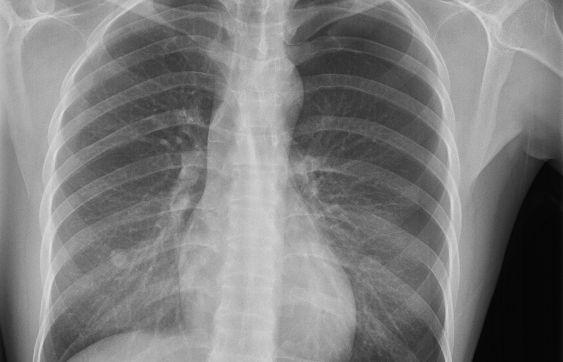

MRI Brain X-Ray

X-Ray